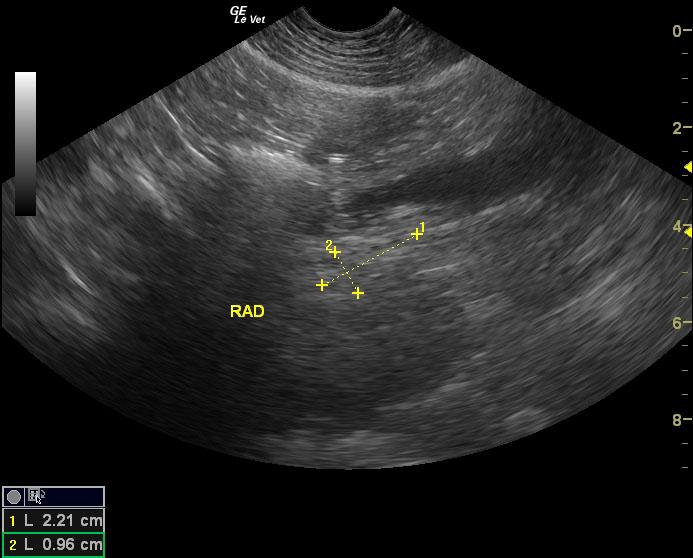

The right adrenal gland was isoechoic to surrounding fat. It measured 2.1 x 0.9 cm. The left adrenal gland comprised a 7.9 x 5.3 cm strongly vascular mass noted on power flow Doppler. Invasion into the left phrenicoabdominal vein was noted. However, the vena cava was not invaded at this time.